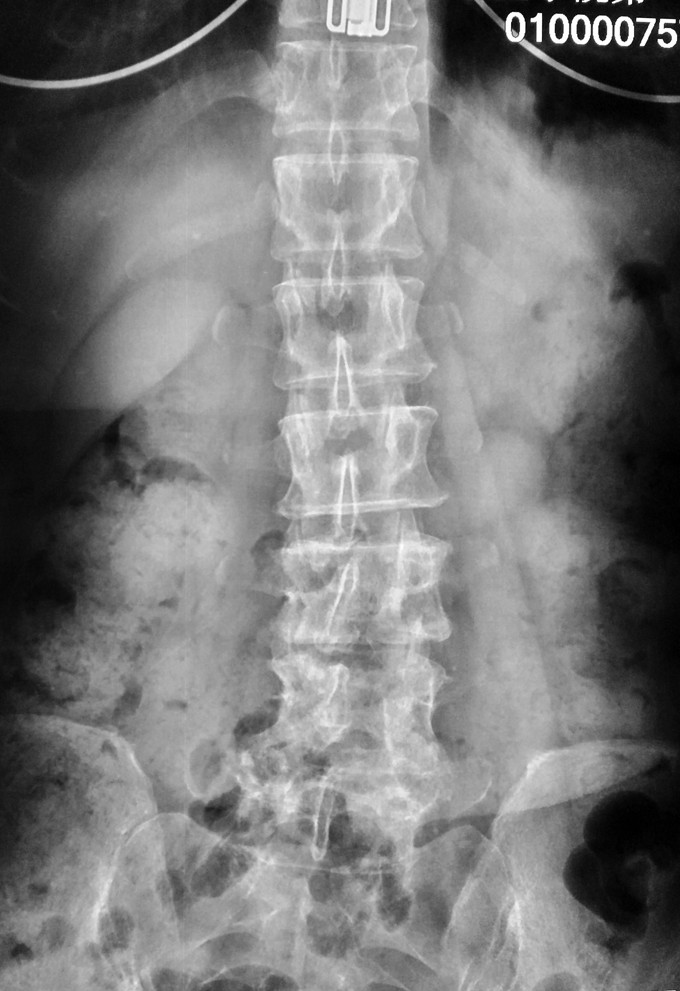

患者女性,58岁。 腰痛间断性发作2年,加重伴左下肢疼痛不适4月 疼痛以久坐和劳累后症状明显,近4月上述症状加重,伴有左下肢麻木疼痛感,经卧床休息后不能缓解。

腰3-4/4-5间隙及椎板压痛及叩击痛,无明显下肢放射痛。左大腿前外侧及膝以下感觉有减退,左侧髋、膝肌力5级,拇趾背伸肌力4级,肌张力不高,左下肢直腿抬高试验40°阳性,加强试验阳性。右下肢感觉肌力正常。 血沉 99mm/h C反应蛋白:4.1ng/L 斑点试验:抗A 111,kangB 127

1.腰3-4结核 2.腰4-5椎管狭窄 因术前血沉比较高,所以予以HREZS抗痨治疗2周,血沉至44mm/h,患者一般情况较前好转。安排手术治疗:后路腰3-4椎间病灶清除椎板植骨+腰4-5减压植骨内固定融合术。